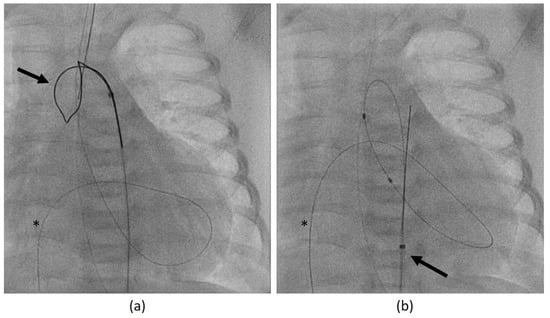

- In case 2, there was an air embolism in the left ventricle during the patient’s first catheterization. Due to depressed LV function with low contractility, the air bubble remained ventrally in the LV (Figure 8), where we managed to extract it with the catheter.

- In the same patient, an aortic wall injury resulting in a constriction of the intima following the second BAV occurred (Figure 9). However, this constriction was without significant stenosis and was corrected at the time of necessary aortic valve repair.